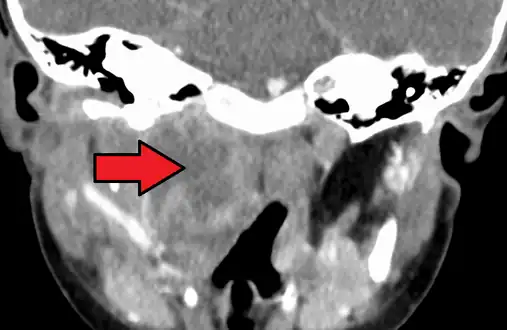

A computed tomography (CT) scan is the definitive diagnostic imaging test.[4]